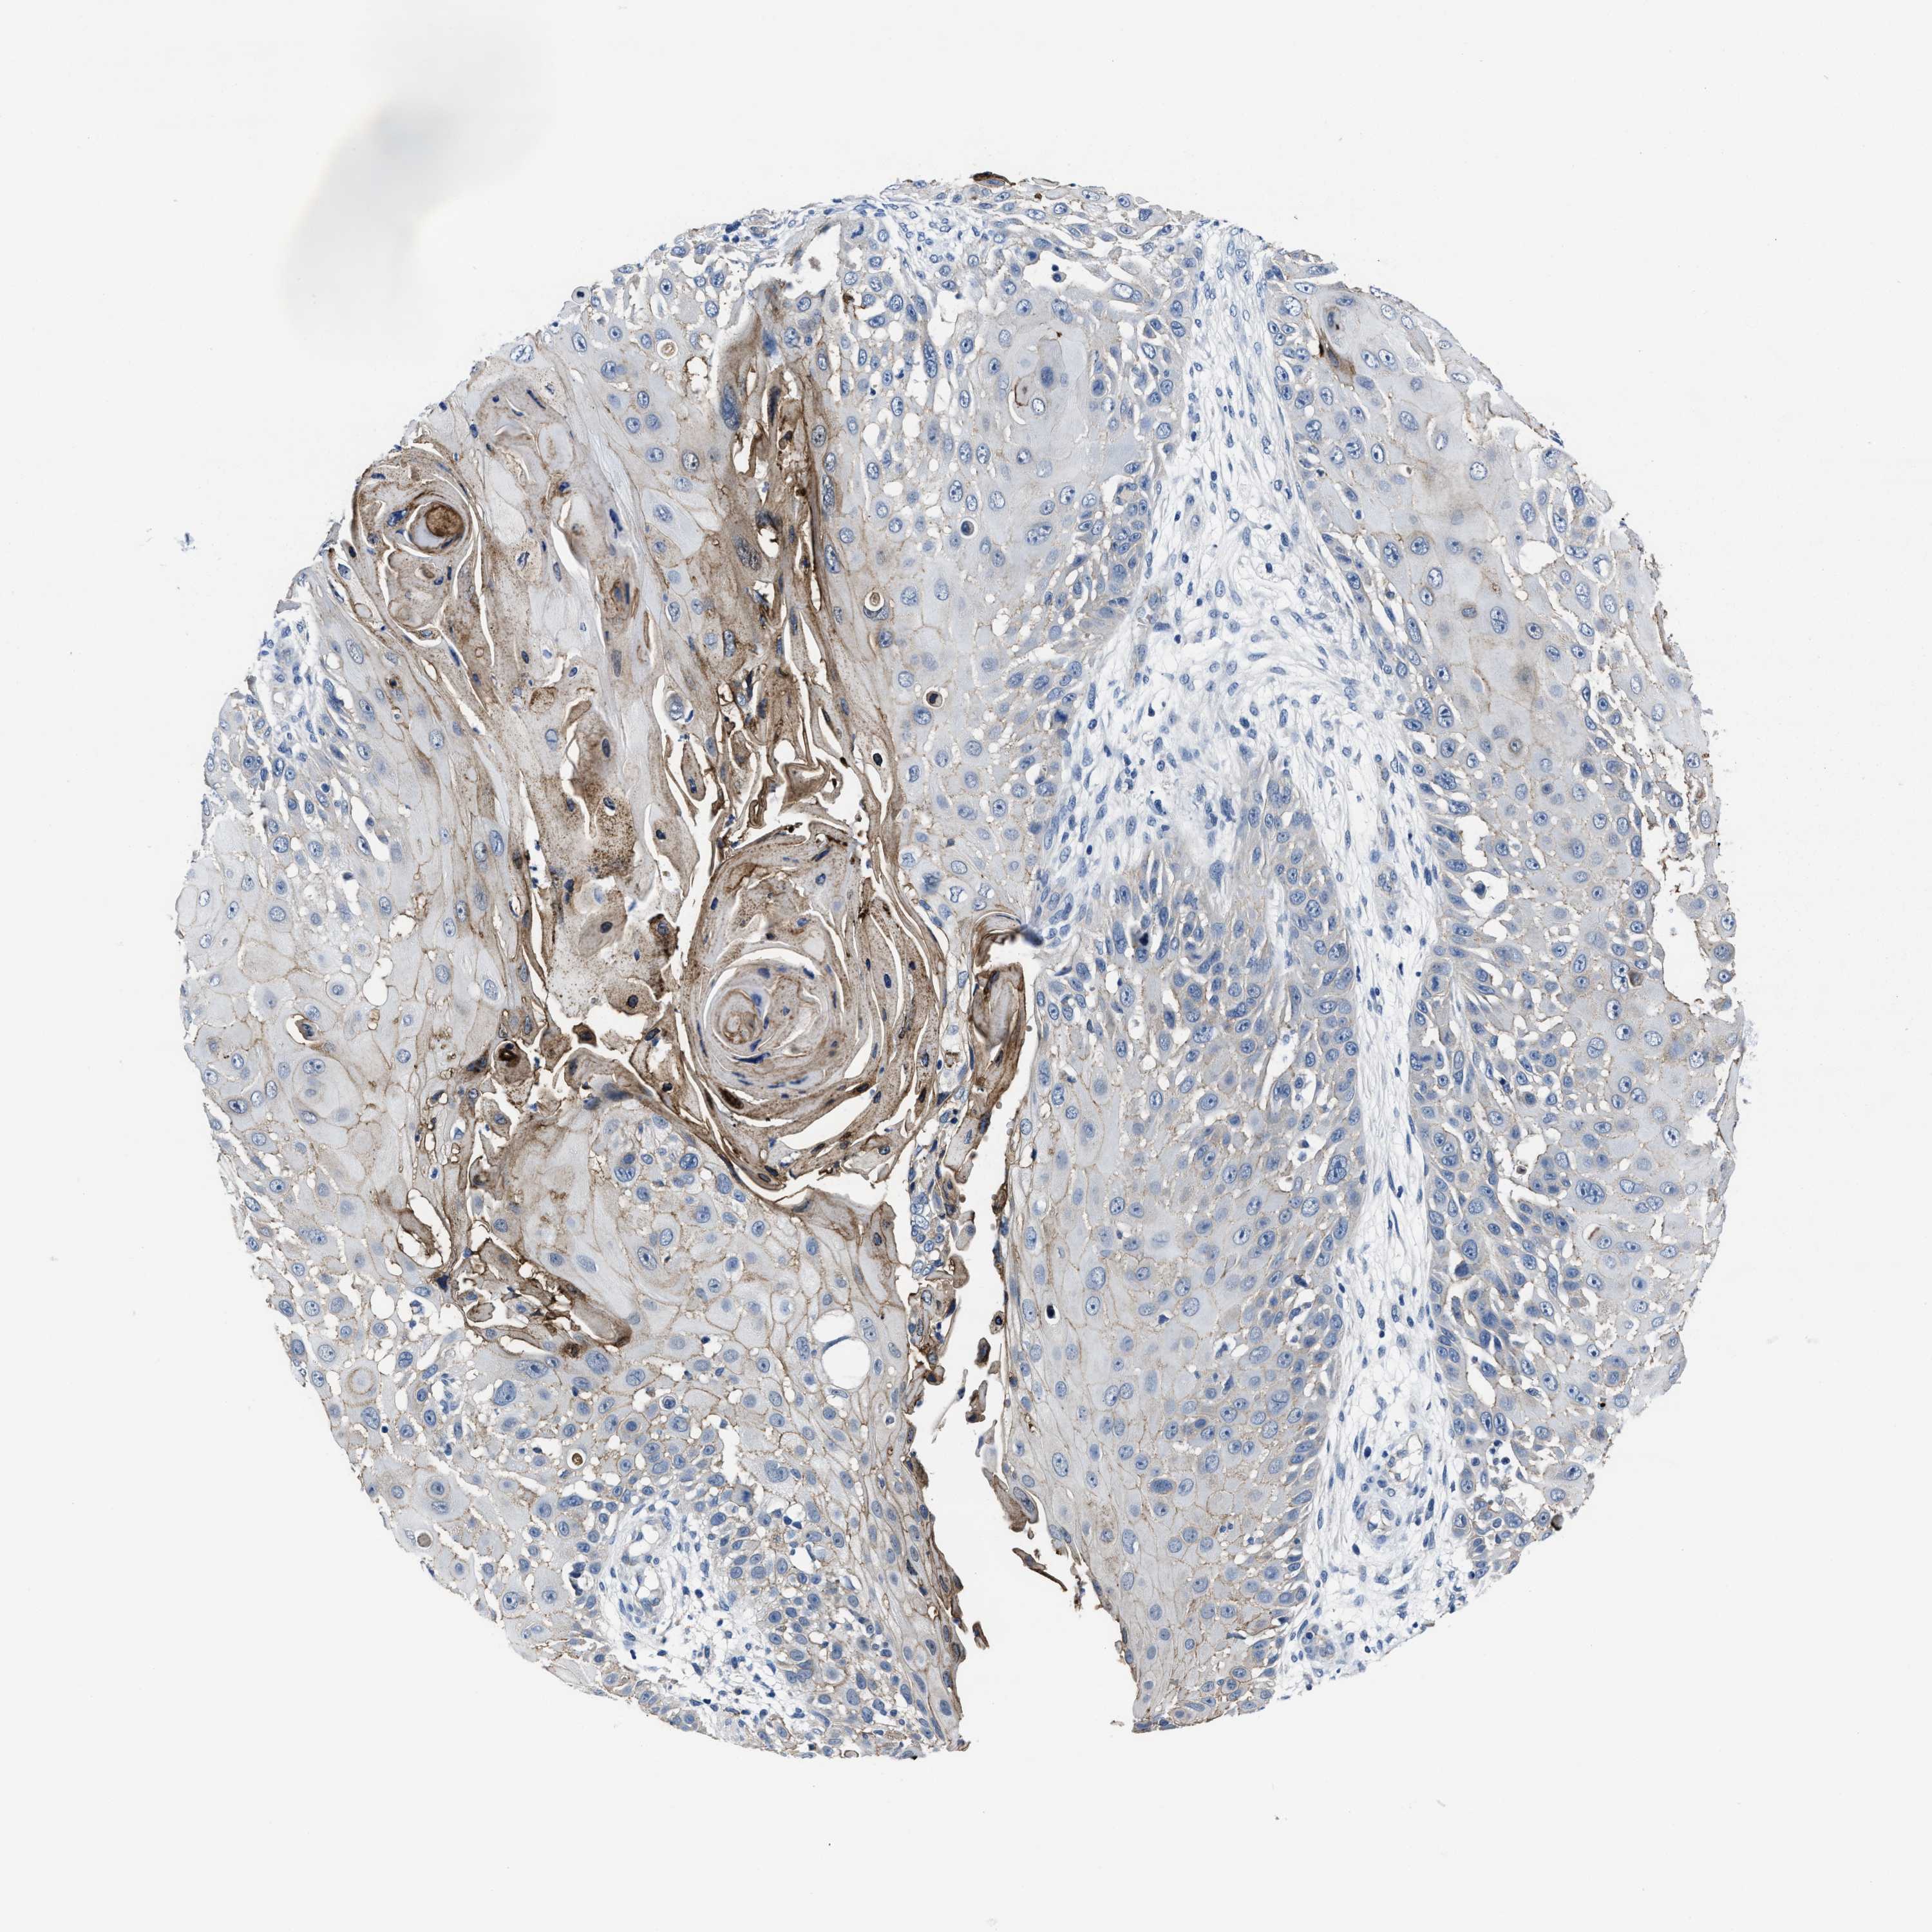

SKIN CANCER - Protein expressioni

A mouse-over function shows sample information and annotation data. Click on an image to view it in a full screen mode. Samples can be filtered based on level of antibody staining by selecting one or several of the following categories: high, medium, low and not detected. The assay and annotation is described here.

Antibody stainingi

Antibody staining in the annotated cell types in the current human tissue is reported as not detected, low, medium, or high, based on conventional immunohistochemistry profiling in selected tissues. This score is based on the combination of the staining intensity and fraction of stained cells.

Each image is clickable and will lead to virtual microscopy that enables deeper exploration of all samples and also displays staining intensity scores, fraction scores and subcellular localization as well as patient and tissue information for each sample.

Antibody HPA016464

Antibody HPA061664

Basal cell carcinoma

Squamous cell carcinoma, NOS

Squamous cell carcinoma, metastatic, NOS

BCC, high aggressive